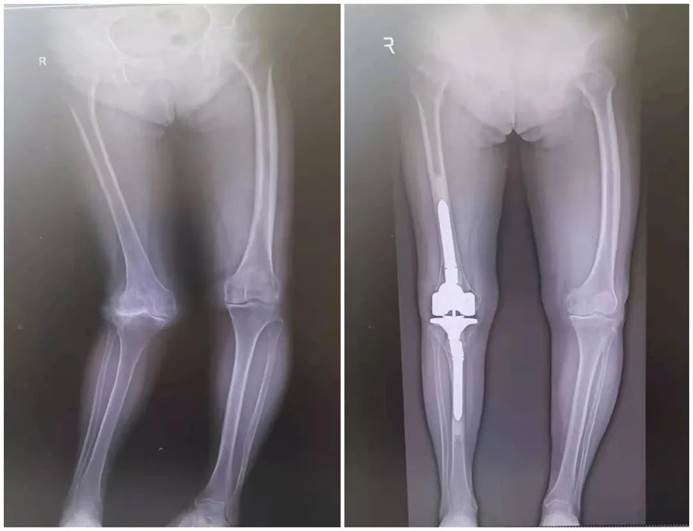

人工关节置换术:适用于关节疾病严重、无法通过保守治疗缓解的患者。该手术通过移除患者的受损关节部位,用人工关节替代受损关节,以恢复关节功能。随着科技不断创新和发展,人工关节置换术符合人体生物力学原理,能够最大程度减轻患者关节疼痛,挽救了中晚期严重的病变关节,使患者能够早期下床,早期改善负重,避免心肺功能衰竭、感染、压疮等临床并发症发生。

人工全膝关节置换术